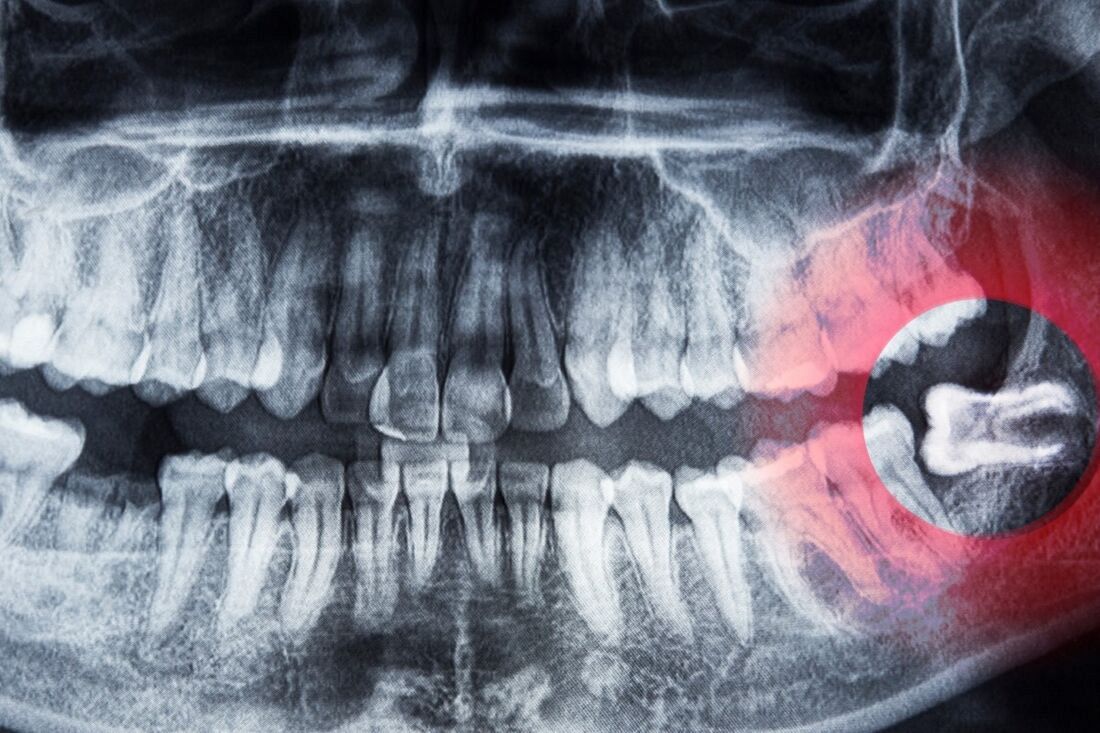

Zęby mądrości to trzecie trzonowce, które wyrzynają się najpóźniej – zwykle między 17. a 25. rokiem życia. U wielu osób w jamie ustnej brakuje jednak miejsca na ich prawidłowe ustawienie. W efekcie ząb może:

- pozostać całkowicie w kości (ząb zatrzymany),

- wyrznąć się częściowo,

- rosnąć pod nieprawidłowym kątem, napierając na sąsiednie zęby.

Właśnie dlatego – jak podkreśla lek. stom. Bartłomiej Warchoł – konsultacja chirurgiczna po wykonaniu zdjęcia pantomograficznego pozwala odpowiednio wcześnie zaplanować ewentualny zabieg i uniknąć nagłych stanów zapalnych.